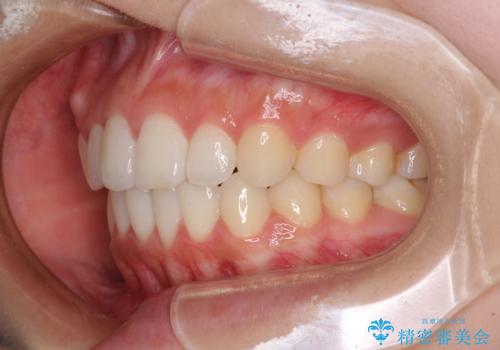

前歯のデコボコと突出感 インビザラインで改善

- 上下前歯のデコボコを気にして来院された患者様です。

インビザラインによる上下歯列の側方拡大と後方移動、IPR(歯と歯の間を削る)にるスペースの獲得により歯列を整えることとしました。

骨格的な左右差があったため、上下の正中を合わせることは困難かと思われましたが、何とか合わせることができました。

一方、骨格の差は改善できないため、奥歯の咬み合わせに物足りなさを感じました。

奥歯の咬み合わせによる不自由はなく、患者様に大変満足していただきました。